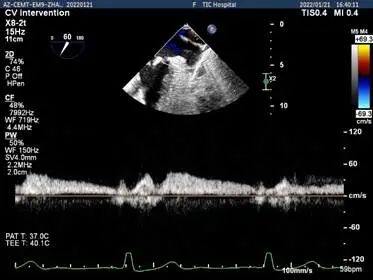

二尖瓣反流频谱呈全收缩期

肺静脉血流频谱呈收缩期反向

肺静脉血流频谱恢复正向